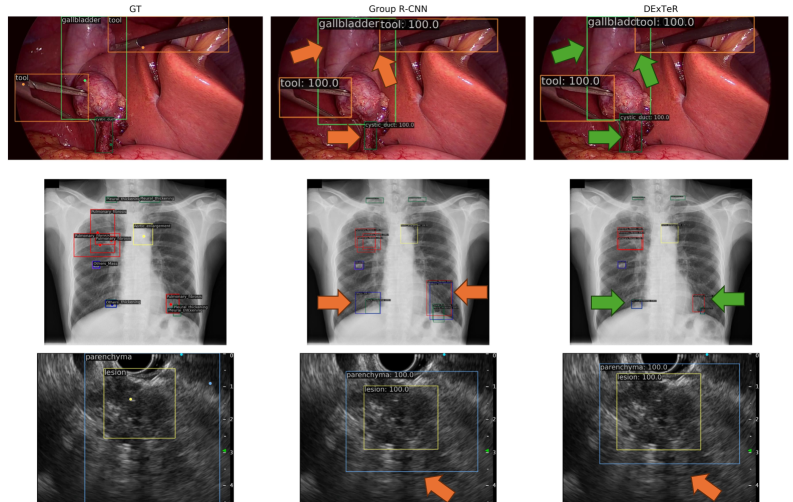

Fig. 7: Qualitative results for Endoscapes, VinDr-CXR, and EUS-D130 datasets (rows). The first column shows the ground truth bounding boxes and point prompts. The second column presents predictions from Group R-CNN, and the third column shows predictions from DExTeR.

We present qualitative results in Fig. 6 for the 12.5% setting. DExTeR demonstrates superior performance, producing tighter boxes that better fit objects (rows 1 and 2). In contrast, Group-RCNN often generates overly wide boxes and struggles to distinguish close instances (row 2). DExTeR effectively leverages prior class and instance information, addressing these issues. However, row 3 highlights a failure case where the predicted box for the pancreas does not fully encompass the organ.